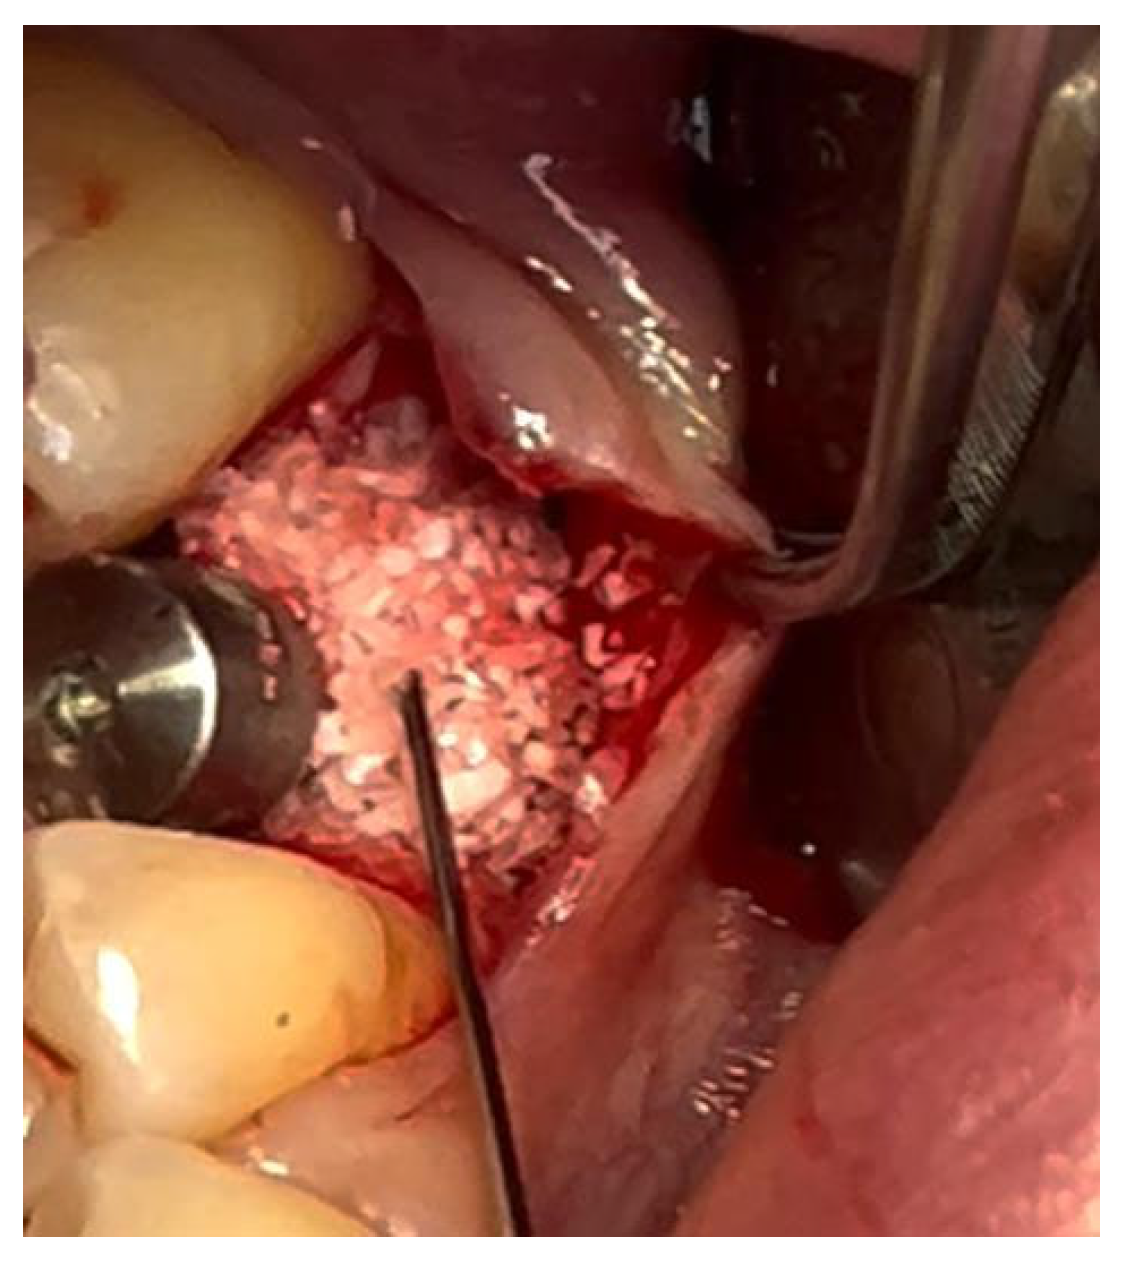

In a 49-year-old patient with ischemic heart disease, Glubran II was used as a stabilizing material for natural bone graft granules at a site rehabilitated with implant-prosthetic treatment, with the aim of achieving volumetric enhancement of the buccal bone. Following specific guidelines for surgical treatment of ischemic heart disease (4), implant therapy was carried out (Figure 8). Natural bone graft material (Bio-Oss®—Geistlich, Baden-Baden, Germany) was applied and stabilized with Glubran II. The application was made using an endodontic needle, depositing single droplets of the glue to cover the entire graft material before placing the prepared flap on top (Figure 9). This technique achieved stable graft fixation at the recipient site, demonstrating the efficacy of Glubran II for internal use (Figure 10).

Figure 9. Stabilization of bone regeneration material with Glubran II.

Materials 18 02642 g009

Figure 10. Surgical site at the end of the polymerization time of Glubran II; the site was subjected to tensile testing, with positive results under the applied tensions.